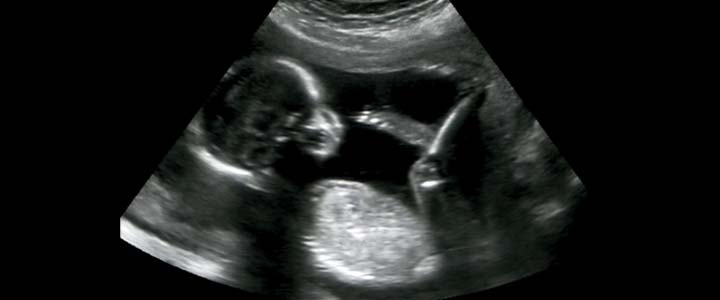

De combinatietest bestaat uit twee onderdelen, namelijk een echo, om de dikte van je kindjes nekplooi te bepalen, en bloedafname bij jou. De echo voor de nekplooimeting vindt plaats tussen 11 weken plus 4 dagen en 13 weken plus 4 dagen zwangerschap. De bloedafname moet gebeuren tussen 8 weken en 13 weken plus 6 dagen zwangerschap. Het beste moment voor de bloedafname is bij een zwangerschap van 10 weken.